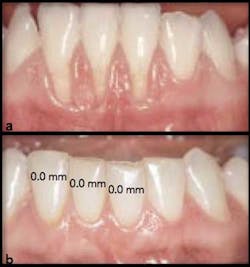

Fig. 5: Free gingival graft 30 years follow up — (a) before, (b) after. (From Pini Prato et al, 2012)